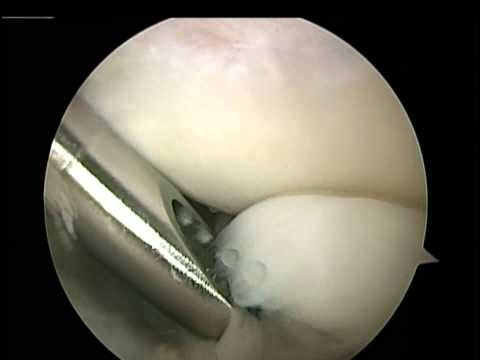

Elbow arthroscopy for Arthritis, Bone spurs and Loose bodies - Dr. Laith Farjo

Elbow arthroscopy is an excellent tool to treat arthritis of the elbow. Often patients lose range of motion and the ability to fully extend their elbow. By removing the bone spurs and loose pieces of cartilage and bone that occurs in arthritis, arthroscopy can achieve relief of pain and improved function with very small incisions.